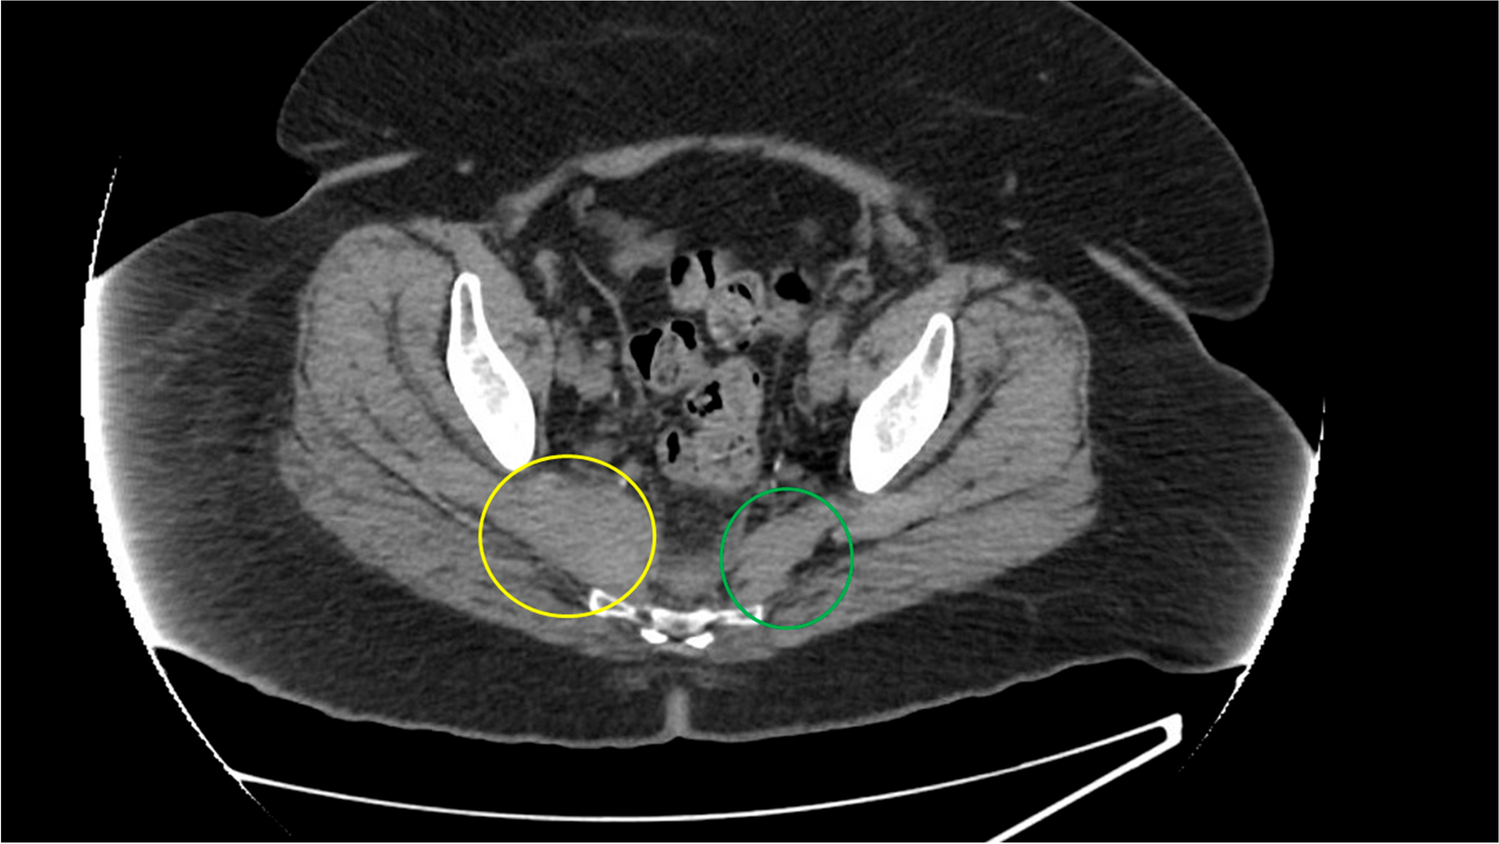

Fig. 2

Sagittal view with orange arrow pointing to the pyriformis hematoma